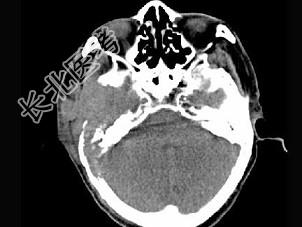

- 单项选择题男,56岁, 右侧腮腺疼痛肿胀半年,CT检查如图, 最可能的诊断是 ( )

A、右侧腮腺炎

B、右侧腮腺混合瘤

C、右侧腮腺癌

D、右侧腮腺转移瘤

E、右侧腮腺淋巴瘤